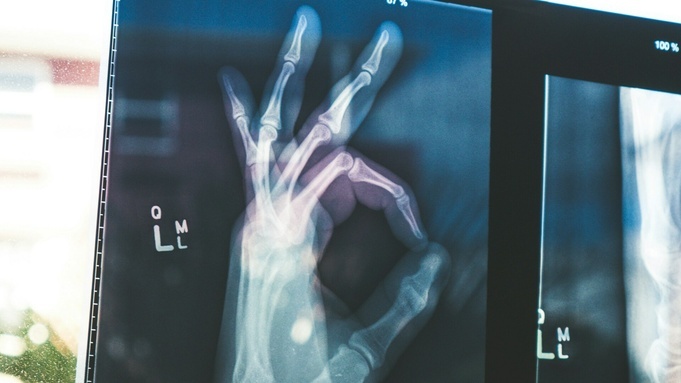

В Барнауле суд приостановил деятельность частного консультативно-диагностического центра "Добрый доктор" в части использования рентгеновского аппарата. Оборудование эксплуатировалось без необходимого разрешения, сообщает объединенная пресс-служба судов Алтайского края.

В ходе рассмотрения дела было установлено, что рентгеновский аппарат MATRIX HP 32 использовался без санитарно-эпидемиологического заключения, подтверждающего соответствие условий работы с источниками ионизирующего излучения, что является нарушением ряда требований.

По решению Индустриального районного суда деятельность ООО КДЦ "Добрый доктор" в части эксплуатации рентгеновского оборудования приостановлена на 20 суток.